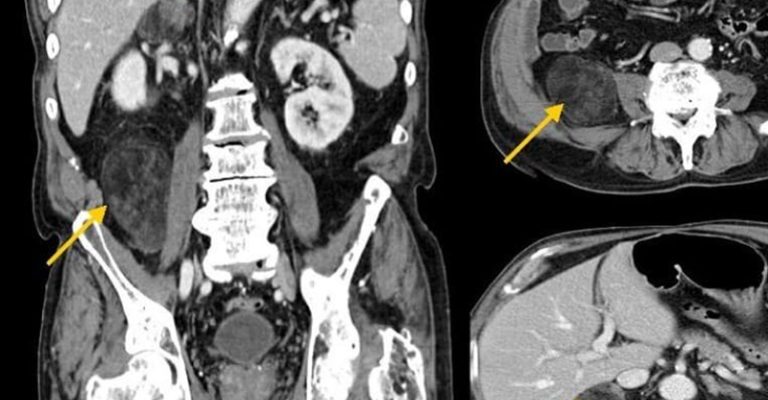

Batın MR, karın bölgesindeki organların manyetik rezonans görüntüleme yöntemiyle detaylı bir şekilde incelenmesini sağlayan bir tıbbi tetkiktir. Manyetik alanlar ve radyo dalgaları kullanılarak, vücut içindeki yumuşak dokuların net ve ayrıntılı görüntüleri elde edilir. Bu yöntem, karaciğer, böbrekler, pankreas, bağırsaklar, dalak gibi organların yanı sıra, karın boşluğundaki damar ve lenf düğümlerini de incelemekte kullanılır.

Batın MR, karın bölgesindeki organ ve dokuların detaylı incelenmesi gerektiğinde çekilir. Doktorlar, karaciğer hastalıkları, pankreas sorunları, böbrek anomalileri, bağırsak iltihaplanmaları veya tümörleri gibi durumları teşhis etmek amacıyla batın MR’ı tercih edebilirler.

Batın emarı, karın bölgesinde açıklanamayan ağrı, kitle veya anormallik tespit edildiğinde çekilir. Özellikle, karaciğer yağlanması, hepatit, safra kesesi taşları, pankreatit gibi durumlar araştırılırken kullanılır. Aynı zamanda, kronik böbrek hastalıkları, bağırsak hastalıkları ve karın içi enfeksiyonlar gibi durumların değerlendirilmesinde de önemli bir araçtır.

Batın MR, karaciğer sirozu, hepatit, pankreas kanseri, safra kesesi taşları, böbrek kistleri ve tümörleri, bağırsak tıkanıklıkları ve iltihaplanmaları gibi birçok hastalığın teşhisinde kullanılır.